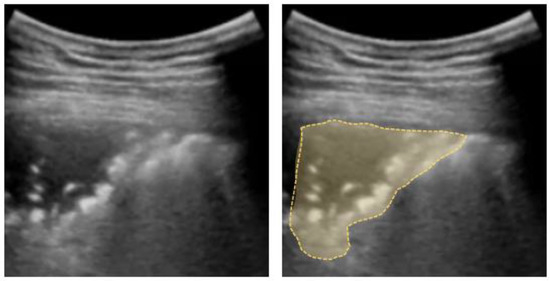

4.3. Lung Consolidation